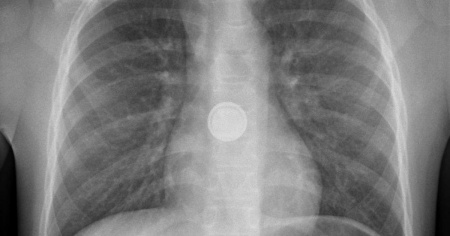

È quanto ha rischiato il piccolo Elias*, un bimbo di dieci mesi che aveva improvvisamente smesso di mangiare. I genitori lo hanno portato al pronto soccorso dell'ospedale pediatrico, dove una radiografia ha permesso d'identificare un corpo estraneo all'interno dell'esofago. Un intervento d'urgenza sotto anestesia totale ha permesso di rimuoverlo: si trattava di una pila a bottone. Sembra che il bambino l'abbia tolta da un telecomando.